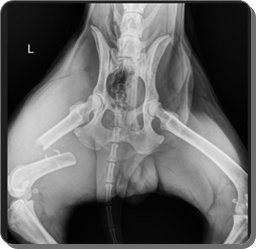

Er wurde auf der Autobahn gefunden, nachdem er von

einem Auto angefahren worden war.

Zoran hatte ein gebrochenes Hinterbein.

Es wurde erfolgreich in der Klinik behandelt, er hat keine Probleme

damit und möchte nun sehr gerne seine eigene Familie.